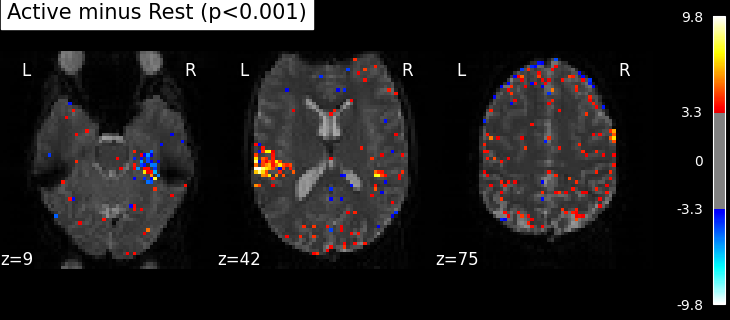

Statistical significance testing. One should worry about the statistical validity of the procedure: here we used an arbitrary threshold of 3.0 but the threshold should provide some guarantees on the risk of false detections (aka type-1 errors in statistics). One suggestion is to control the false positive rate (fpr, denoted by alpha) at a certain level, e.g. 0.001: this means that there is 0.1% chance of declaring an inactive voxel, active.

from nilearn.glm import threshold_stats_img

_, threshold = threshold_stats_img(z_map, alpha=0.001, height_control="fpr")

print(f"Uncorrected p<0.001 threshold: {threshold:.3f}")

plot_stat_map(

z_map,

bg_img=mean_img,

threshold=threshold,

display_mode="z",

cut_coords=3,

black_bg=True,

title="Active minus Rest (p<0.001)",

)

plt.show()

Uncorrected p<0.001 threshold: 3.291